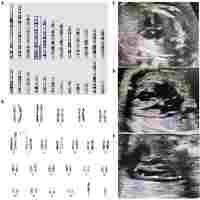

| Abstract | Abstract Background The implementation of genomic testing in pregnancy means that couples have access to more information about their child’s genetic make-up before birth than ever before. One of the resulting challenges is the management of genetic variations with unclear clinical significance. This population-based study will help to close this critical knowledge gap through a multidisciplinary cohort study of children with and without genomic copy number variants (CNVs) diagnosed before birth. By comparing children with prenatally-ascertained CNVs to children without a CNV, we aim to (1) examine their developmental, social-emotional and health status; (2) measure the impact of prenatal diagnosis of a CNV on maternal perceptions of child health, behavior and development; and (3) determine the proportion of prenatally-ascertained CNVs of unknown or uncertain significance that are reclassified as benign or pathogenic after 2 or more years. Methods This study will establish and follow up a cohort of mother-child pairs who have had a prenatal diagnosis with a chromosomal microarray from 2013-2019 in the Australian state of Victoria. Children aged 12 months to 7 years will be assessed using validated, age-appropriate measures. The primary outcome measures will be the Wechsler Preschool and Primary Scale of Intelligence IV (WPSSI-IV) IQ score (2.5 to 7 year old’s), the Ages and Stages Questionnaire (12-30 months old), and the Brief Infant- Toddler Social and Emotional Assessment (BITSEA) score. Clinical assessment by a pediatrician will also be performed. Secondary outcomes will be scores obtained from the: Vineland Adaptive Behavior Scale, Maternal Postnatal Attachment Questionnaire, the Vulnerable Child Scale, Profile of Mood States, Parent Sense of Competence Scale. A descriptive analysis of the reclassification rates of CNVs after ≥2 years will be performed. Discussion This study protocol describes the first Australian cohort study following children after prenatal diagnostic testing with chromosomal microarray. It will provide long-term outcomes of fetal genomic variants to guide evidence-based pre-and postnatal care. This, in turn, will inform future efforts to mitigate the negative consequences of conveying genomic uncertainty during pregnancy. Trial registration ACTRN12620000446965p ; Registered on April 6, 2020. |